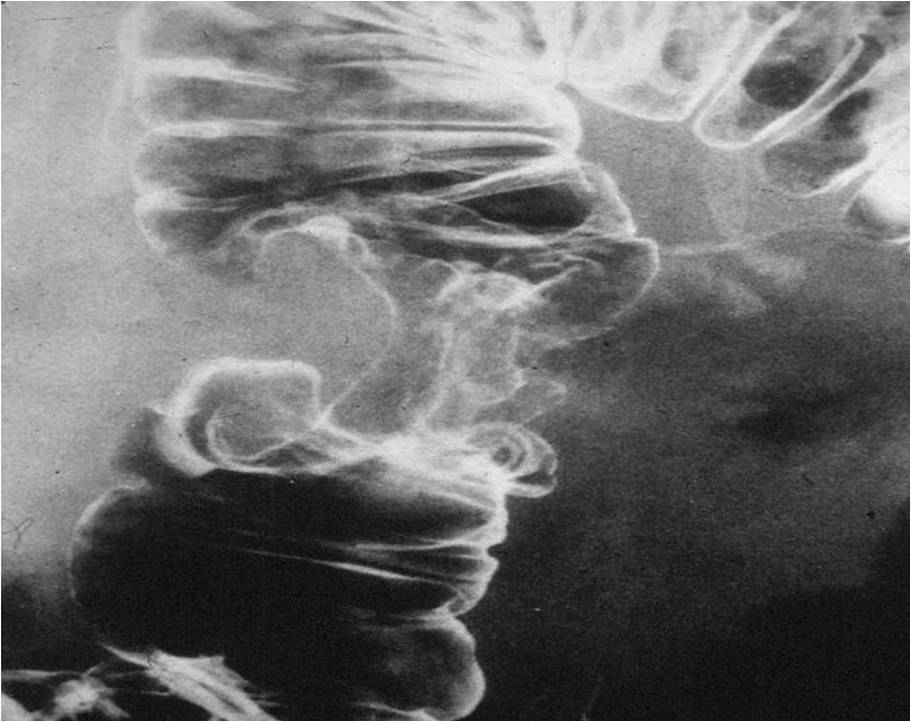

Image

Fig.2.: Achalasia

Radiographic findings: marked dilatation of the esophageal lumen. Luminal diameter can be seriously widened. In advanced cases the tortuous gullet constitutes the mediastinal interface. The cardia shows conical narrowing. The esophageal lumen is filled with undigested food. Opening of the cardia is delayed, emptying is intermittent. The stomach is shrunken. The result is a so called microgaster as the esophagus takes over the stomach’s reservoir function.